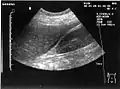

Ultrasound of liver (left side of the image) and right kidney (right side of the image) and Morison's pouch, not containing fluid